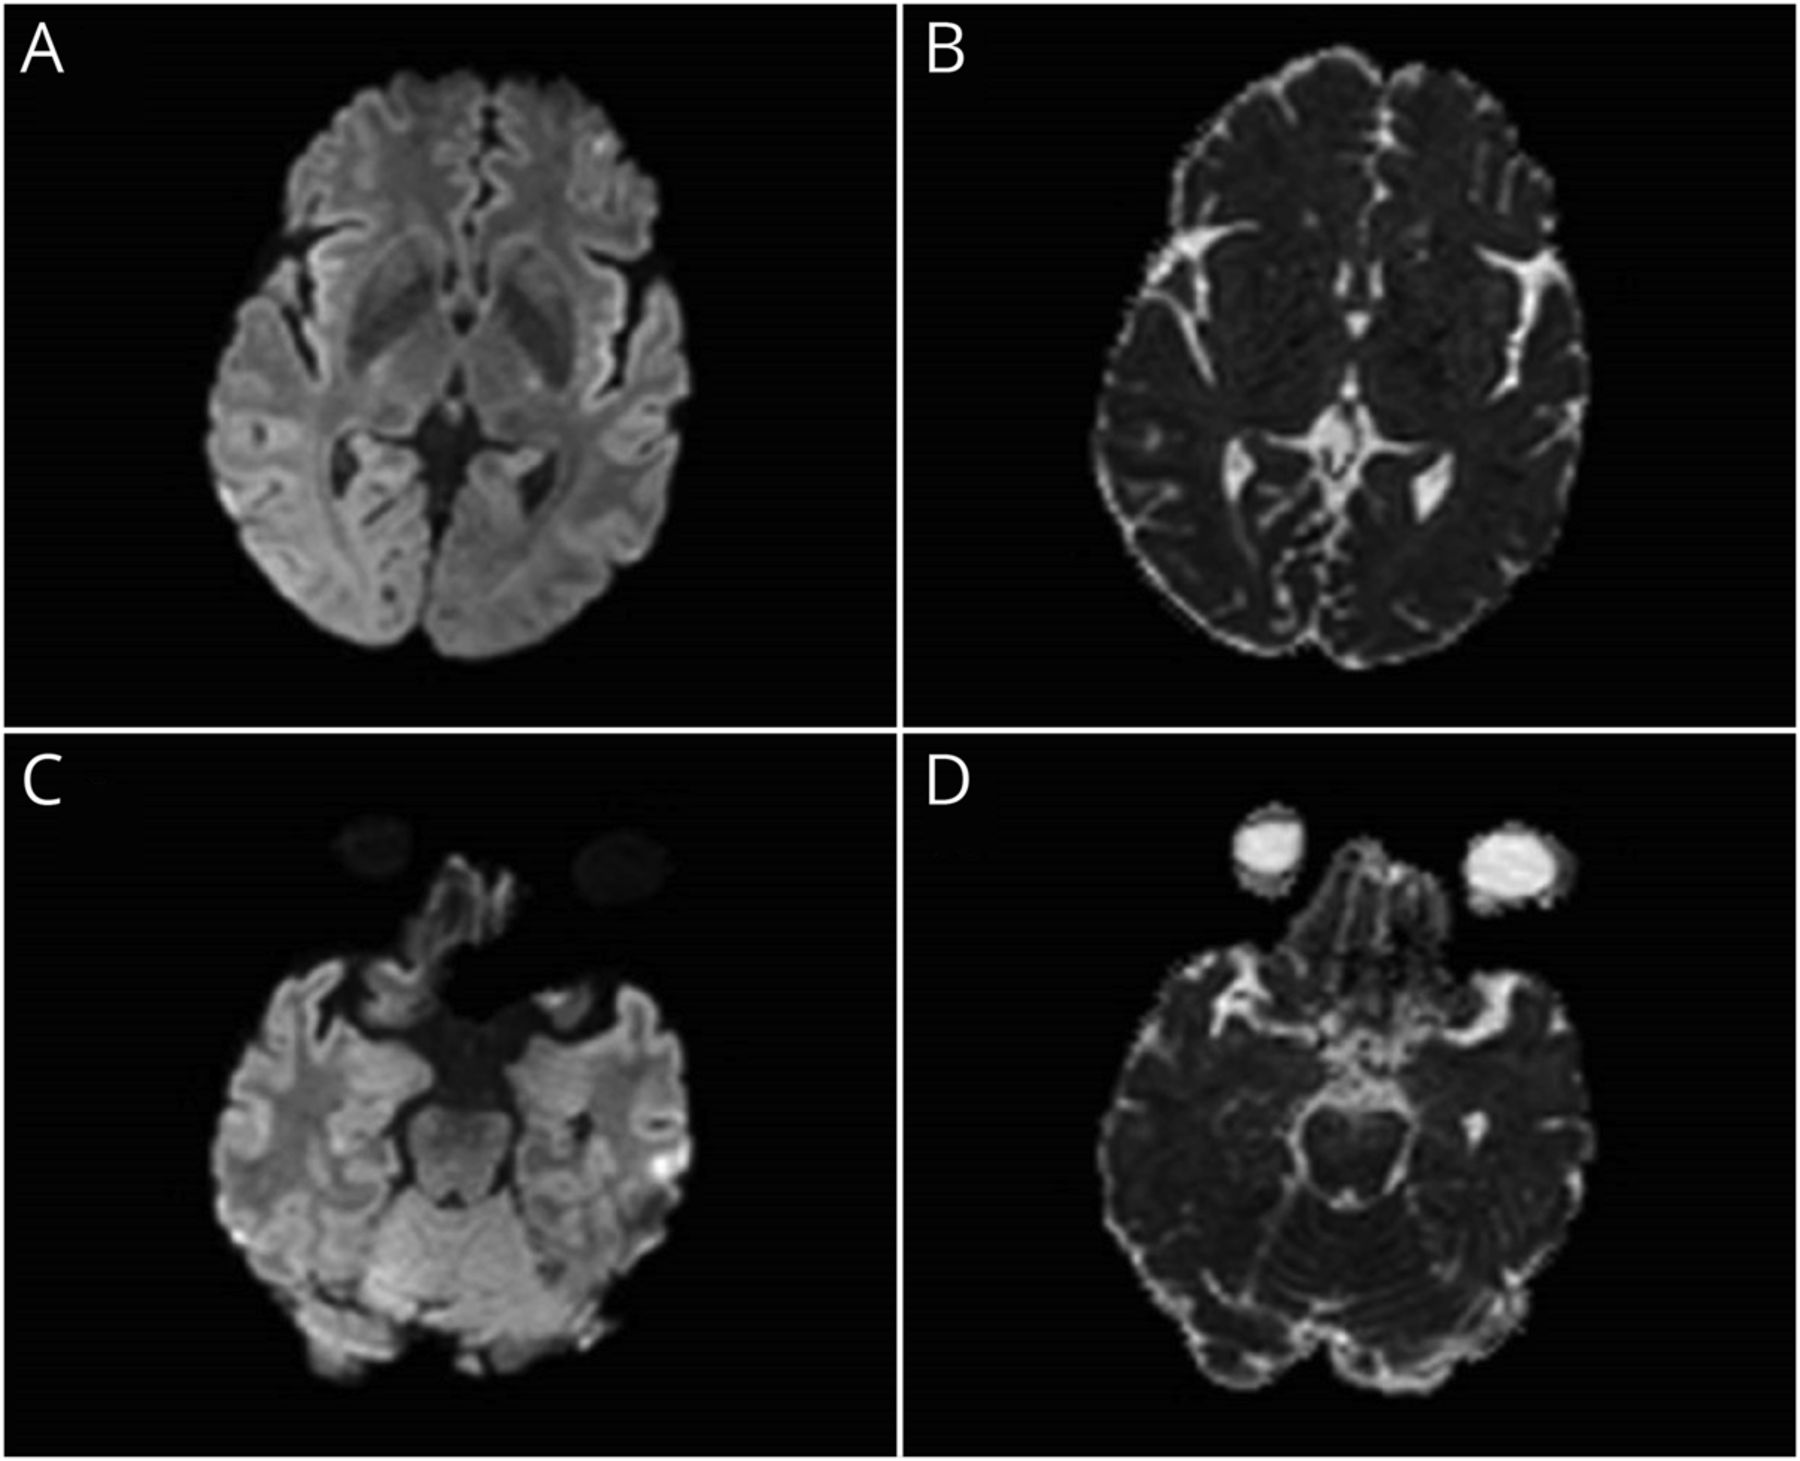

我们与轴向削减显示基底神经节(A和B)和内侧颞叶(C和D) diffusion-weighted成像(驾车)和表观扩散系数(ADC)的MRI序列。没有扩散限制损伤。